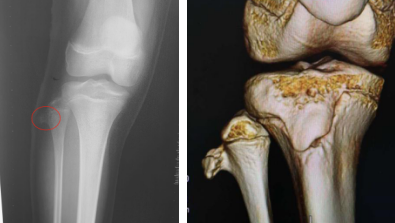

骨软骨瘤,又称外生骨疣,是一种多发于长骨干骺(hóu)端的骨性隆起,起源于软骨生长板的外围,是骨与软骨生长过程中形成的发育畸形,还可见于具有软骨生长的任何骨上。

骨软骨瘤形成于骨成熟前的任何年龄,最初发现年龄一般在5~15岁,男性多于女性。凡软骨化骨的部位均可发生骨软骨瘤,多见于四肢长骨的干骺端和躯干的上下肢带骨,膝关节上下最为常见,其次是腕关节、踝关节、肱骨上端和股骨上端,手足的小骨少见。